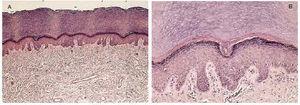

En su libro de 1978 Ackerman distinguió tres clases de hiperortoqueratosis: basket-woven, compact, and laminated1. En la segunda edición del libro, Ackerman et al definieron la primera como «una capa córnea cuyas células se disponen de forma entrecruzada semejando la disposición de una cesta entretejida»2. Esta definición tiene un error y medio. El error consiste en que las células córneas son demasiado pequeñas para formar entrecuzamientos entre ellas, lo que parece cruzarse con las láminas en que se agrupan los corneocitos. Y en segundo lugar esas láminas «semejan» los mimbres entretejidos de un cesto, pero (y éste es el medio error) se trata de una apariencia, no de una realidad; en realidad son láminas onduladas, como las de un hojaldre, que en los cortes histológicos simulan hilos entretejidos (figs. 1 y 2). Por ello nos parece igual de gráfico, pero mucho más ajustado a la realidad hablar de capa córnea hojaldrada (o laxa por el motivo que más adelante explicaremos). Ackerman et al añadían que ésta «es la disposición del estrato córneo de cualquier zona de la piel normal, excepto de palmas y plantas, donde los corneocitos se agrupan de forma compacta»2.

FIG. 1.--Capa córnea laxa (hojaldrada, basket-woven) normal de la epidermis normal que recubre toda la piel excepto en palmas y plantas; es delgada, laxa y basófila. (Hematoxilina-eosina. A: x100; B: x400).

FIG. 2.-- Hiperqueratosis ortoqueratósica (hiperortoqueratosis) laxa en un acantoma de células grandes. Sólo el fragmento epidérmico vertical de la izquierda de A tiene la córnea de espesor normal; la córnea de las piernas es normalmente más gruesa que en otra zonas. (Hematoxilina-eosima. A: x40; B: x400.)